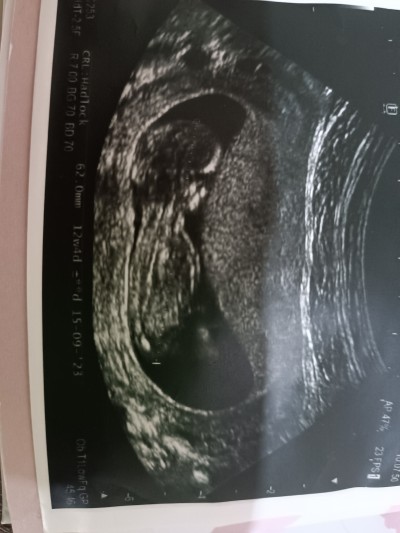

Doktor tahminde bulundu ama yinede merak ettim :)

Belinden aşağısı belli olmuyor ama karanlık çıkmış. Sallayarak erkek diyorum :D

Adaşım :) hayırlı evlat olur inşallah canım. Erkek dediyse genelde değişmiyor. Benim de iki oğlum var. İkisini de 12 haftalıkken öğrendim. Ama benzettim demedi doktor. Erkek bebek diye çok kesin söylemişti bana.

İnşallah sağlıkla gelsin evlat bu cinsiyeti farketmez de kesin konuşmadı işte kafam karıştı :) az daha bekle çünkü değişebilir benzettim dedi

Bi dahaki gittiğinde kesinleşir canım. Allah sağlıklı hayırlı evlat etsin inşallah. Cinsiyet fark etmez tabiiki ama insan merak ediyor yine de :) ama anne hissi doğru bence. Ben ikisini de öğrenir öğrenmez erkek demiştim. Eşim ilk çocukta kız olacak demişti hatta. Erkekler kız çocuk istiyo genelde ondan heralde :) Sen ne hissediyosun :)

Ben kız hissediyorum eşimde erkek hissediyo bilmiyorum artık cuma günü bidaha gidicez sonuç için belki netleşir :))